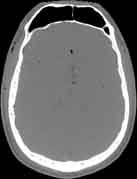

Visible Human male: Sectio transversalis 1079

CT